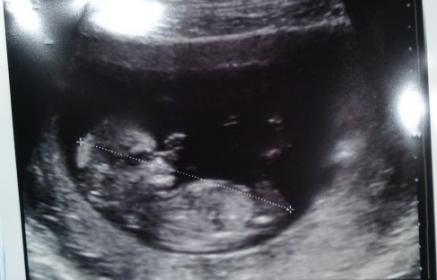

I've been trying to get my head around this nub thing and two friends and myself were talking about my scan photo of my youngest. There was definitely no nub on my eldest scans. But is there on this scan photo?

Attachment 6564